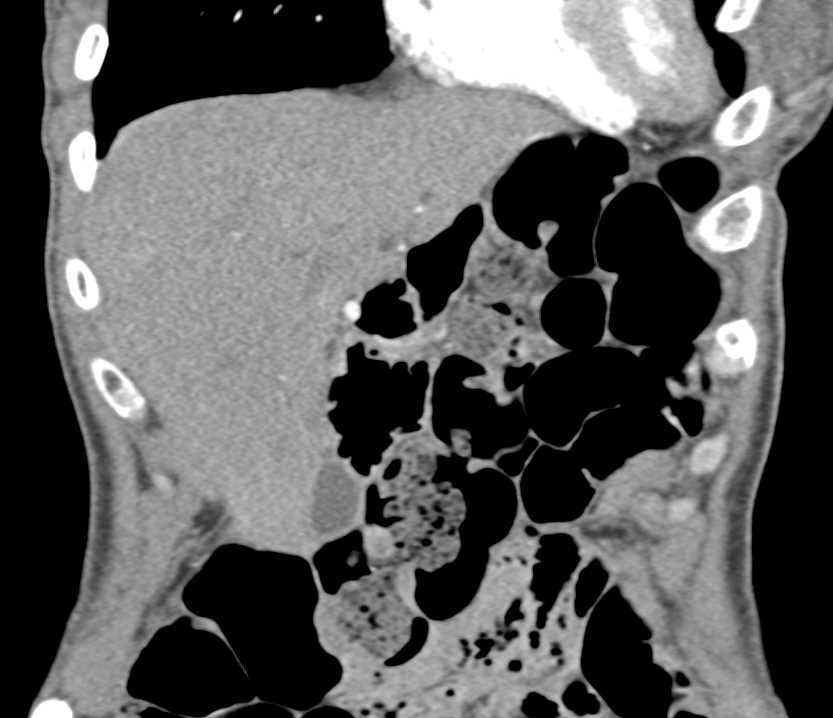

Small Bowel LUQ is Dilated